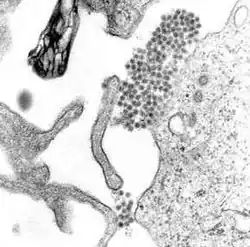

Dengue virus

Dengue virus (DENV)